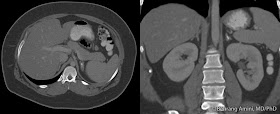

Echinococcal Cyst of the Liver

The liver is the most common location (95% of cases) for infection by Echinococcosis multilocularis, a tapeworm that is endemic in central and northern Europe, northern Asia, Japan, China, Turkey, and parts of North America. Dogs are the definitive hosts and humans, sheep, goats, and other herbivores serve as intermediate hosts. Humans are aberrant intermediate hosts who can develop slowly progressive and life-threatening tumorlike growths in the liver.

Ultrasound reveals an amorphous, heterogeneous, hyperechoic mass sometimes associated with central hypoechoic areas and irregular calcifications. Vascular or biliary invasion may also be seen.

CT has a high sensitivity and is used to determine vascular, biliary, or extrahepatic extension, all of which have implications for resectability. CT findings include an infiltrating mass with irregular margins and calcified or cystic components. Parts of the mass may enhance.